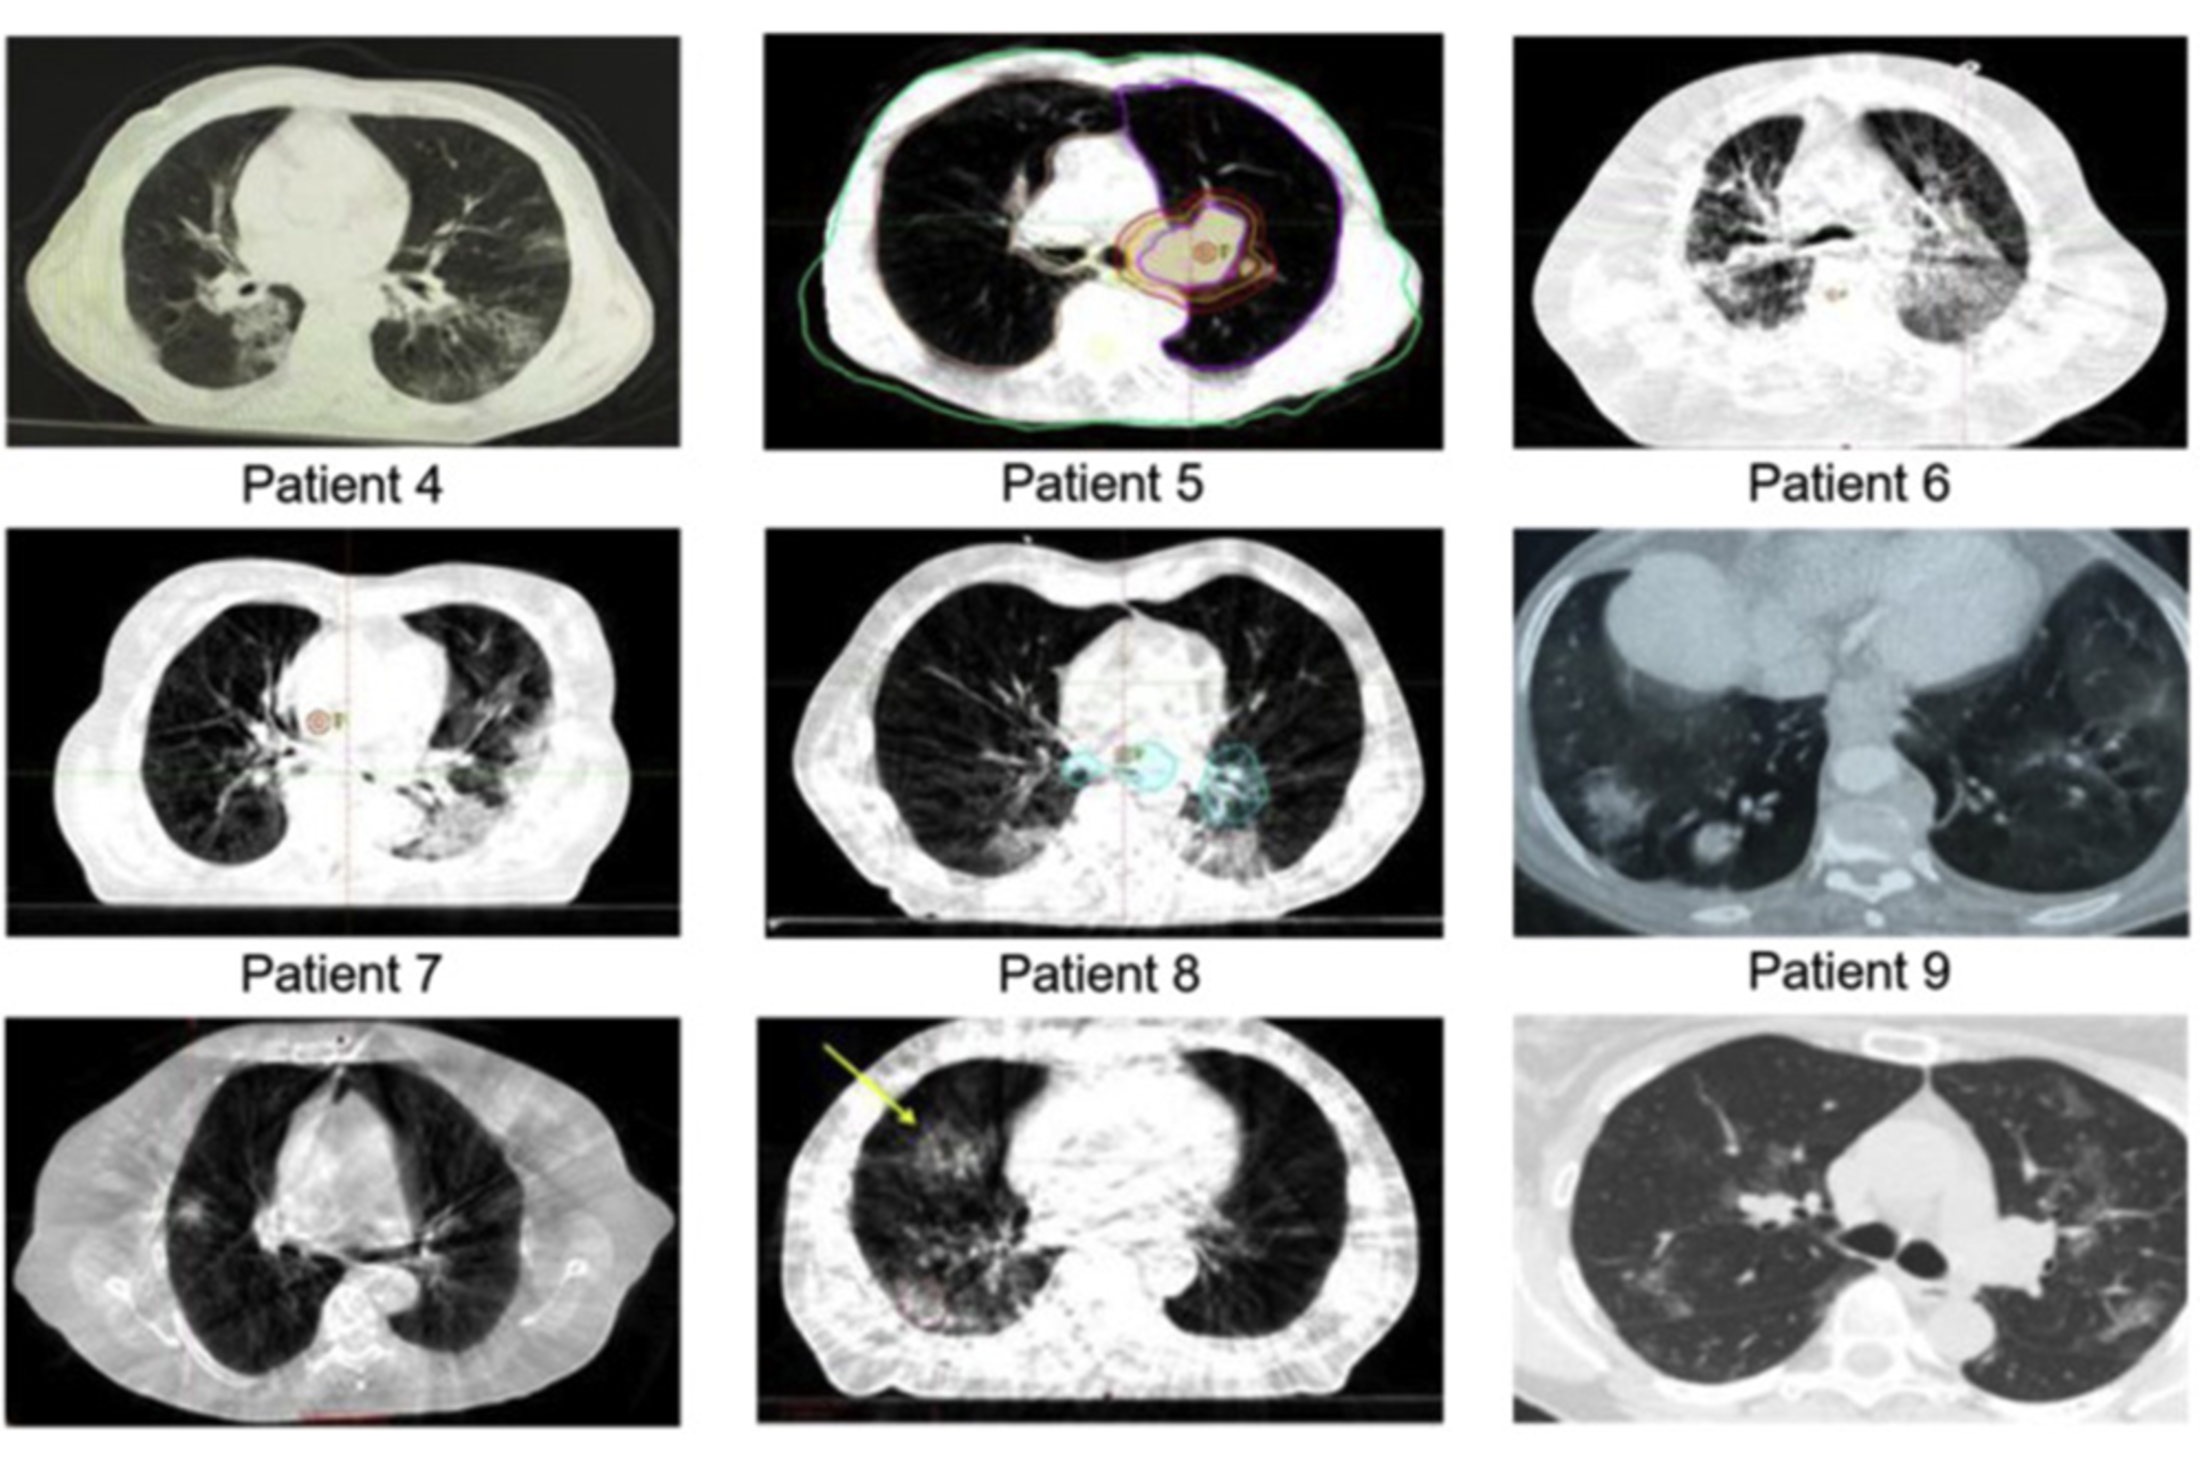

CT scan showing patchy infiltrates in the lungs. Photo provided by the Journal of Thoracic Oncology

In the study, Warren pooled CT scans from several institutions around the world selected from patients who had undergone image-guided radiotherapy and developed COVID-19 during treatment. In the majority of cases studied, the scans revealed the presence of infiltrates, which refers to the hazy gray areas that can show up on scans of the lungs and serves as a marker of COVID-19 before the patient showed any symptoms.

In the study, researchers reviewed the scans of nine lung cancer patients from Turkey, Spain, Belgium, Egypt and the United States who had tested positive for COVID-19. Warren said, surprisingly, that eight out of the nine patient scans revealed the presence of infiltrates in the lungs.